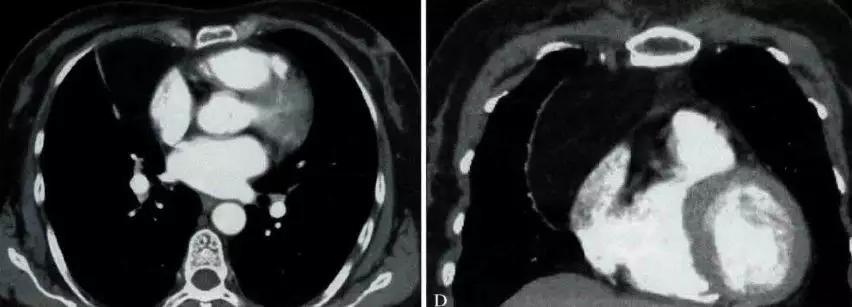

非侵袭性胸腺瘤CT图像

a. CT平扫示前上纵膈主动脉弓与胸骨间软组织密度肿块,密度均匀,边缘浅分叶状 b. CT增强示肿块均匀强化,肿块与主动脉弓之间脂肪间隙清晰

侵袭性胸腺瘤CT图像

a. CT平扫示肺动脉与胸骨间肿块,密度尚均匀,形态不规则b. CT增强示肿块不均匀强化,见低密度囊变区域,肿块与肺动脉之间脂肪间隙消失,肺动脉壁模糊。